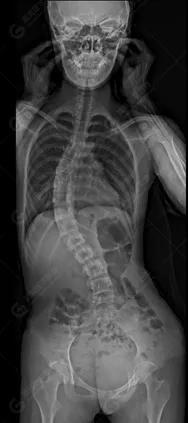

15歲女性,發(fā)現(xiàn)特發(fā)性脊柱側(cè)彎3年,于2019年1月23日來到廣東高尚醫(yī)學(xué)影像診斷中心行EOS檢查,2019年2月行手術(shù)治療后多次到中心行EOS復(fù)查。

2019-01-23

脊柱側(cè)彎最重要一個臨床參數(shù)是側(cè)彎角(Cobb角),目前臨床公認(rèn)的Cobb角>10 °診斷為脊柱側(cè)彎;如Cobb角進行性持續(xù)性增加>40 °需要手術(shù)矯正治療。

本例患者胸椎右側(cè)彎,Cobb角(T6/T12)為47°,遂行手術(shù)矯正治療。術(shù)后多次隨訪的Cobb角(T10/L3)為12°-15°之間,較術(shù)前明顯縮小。